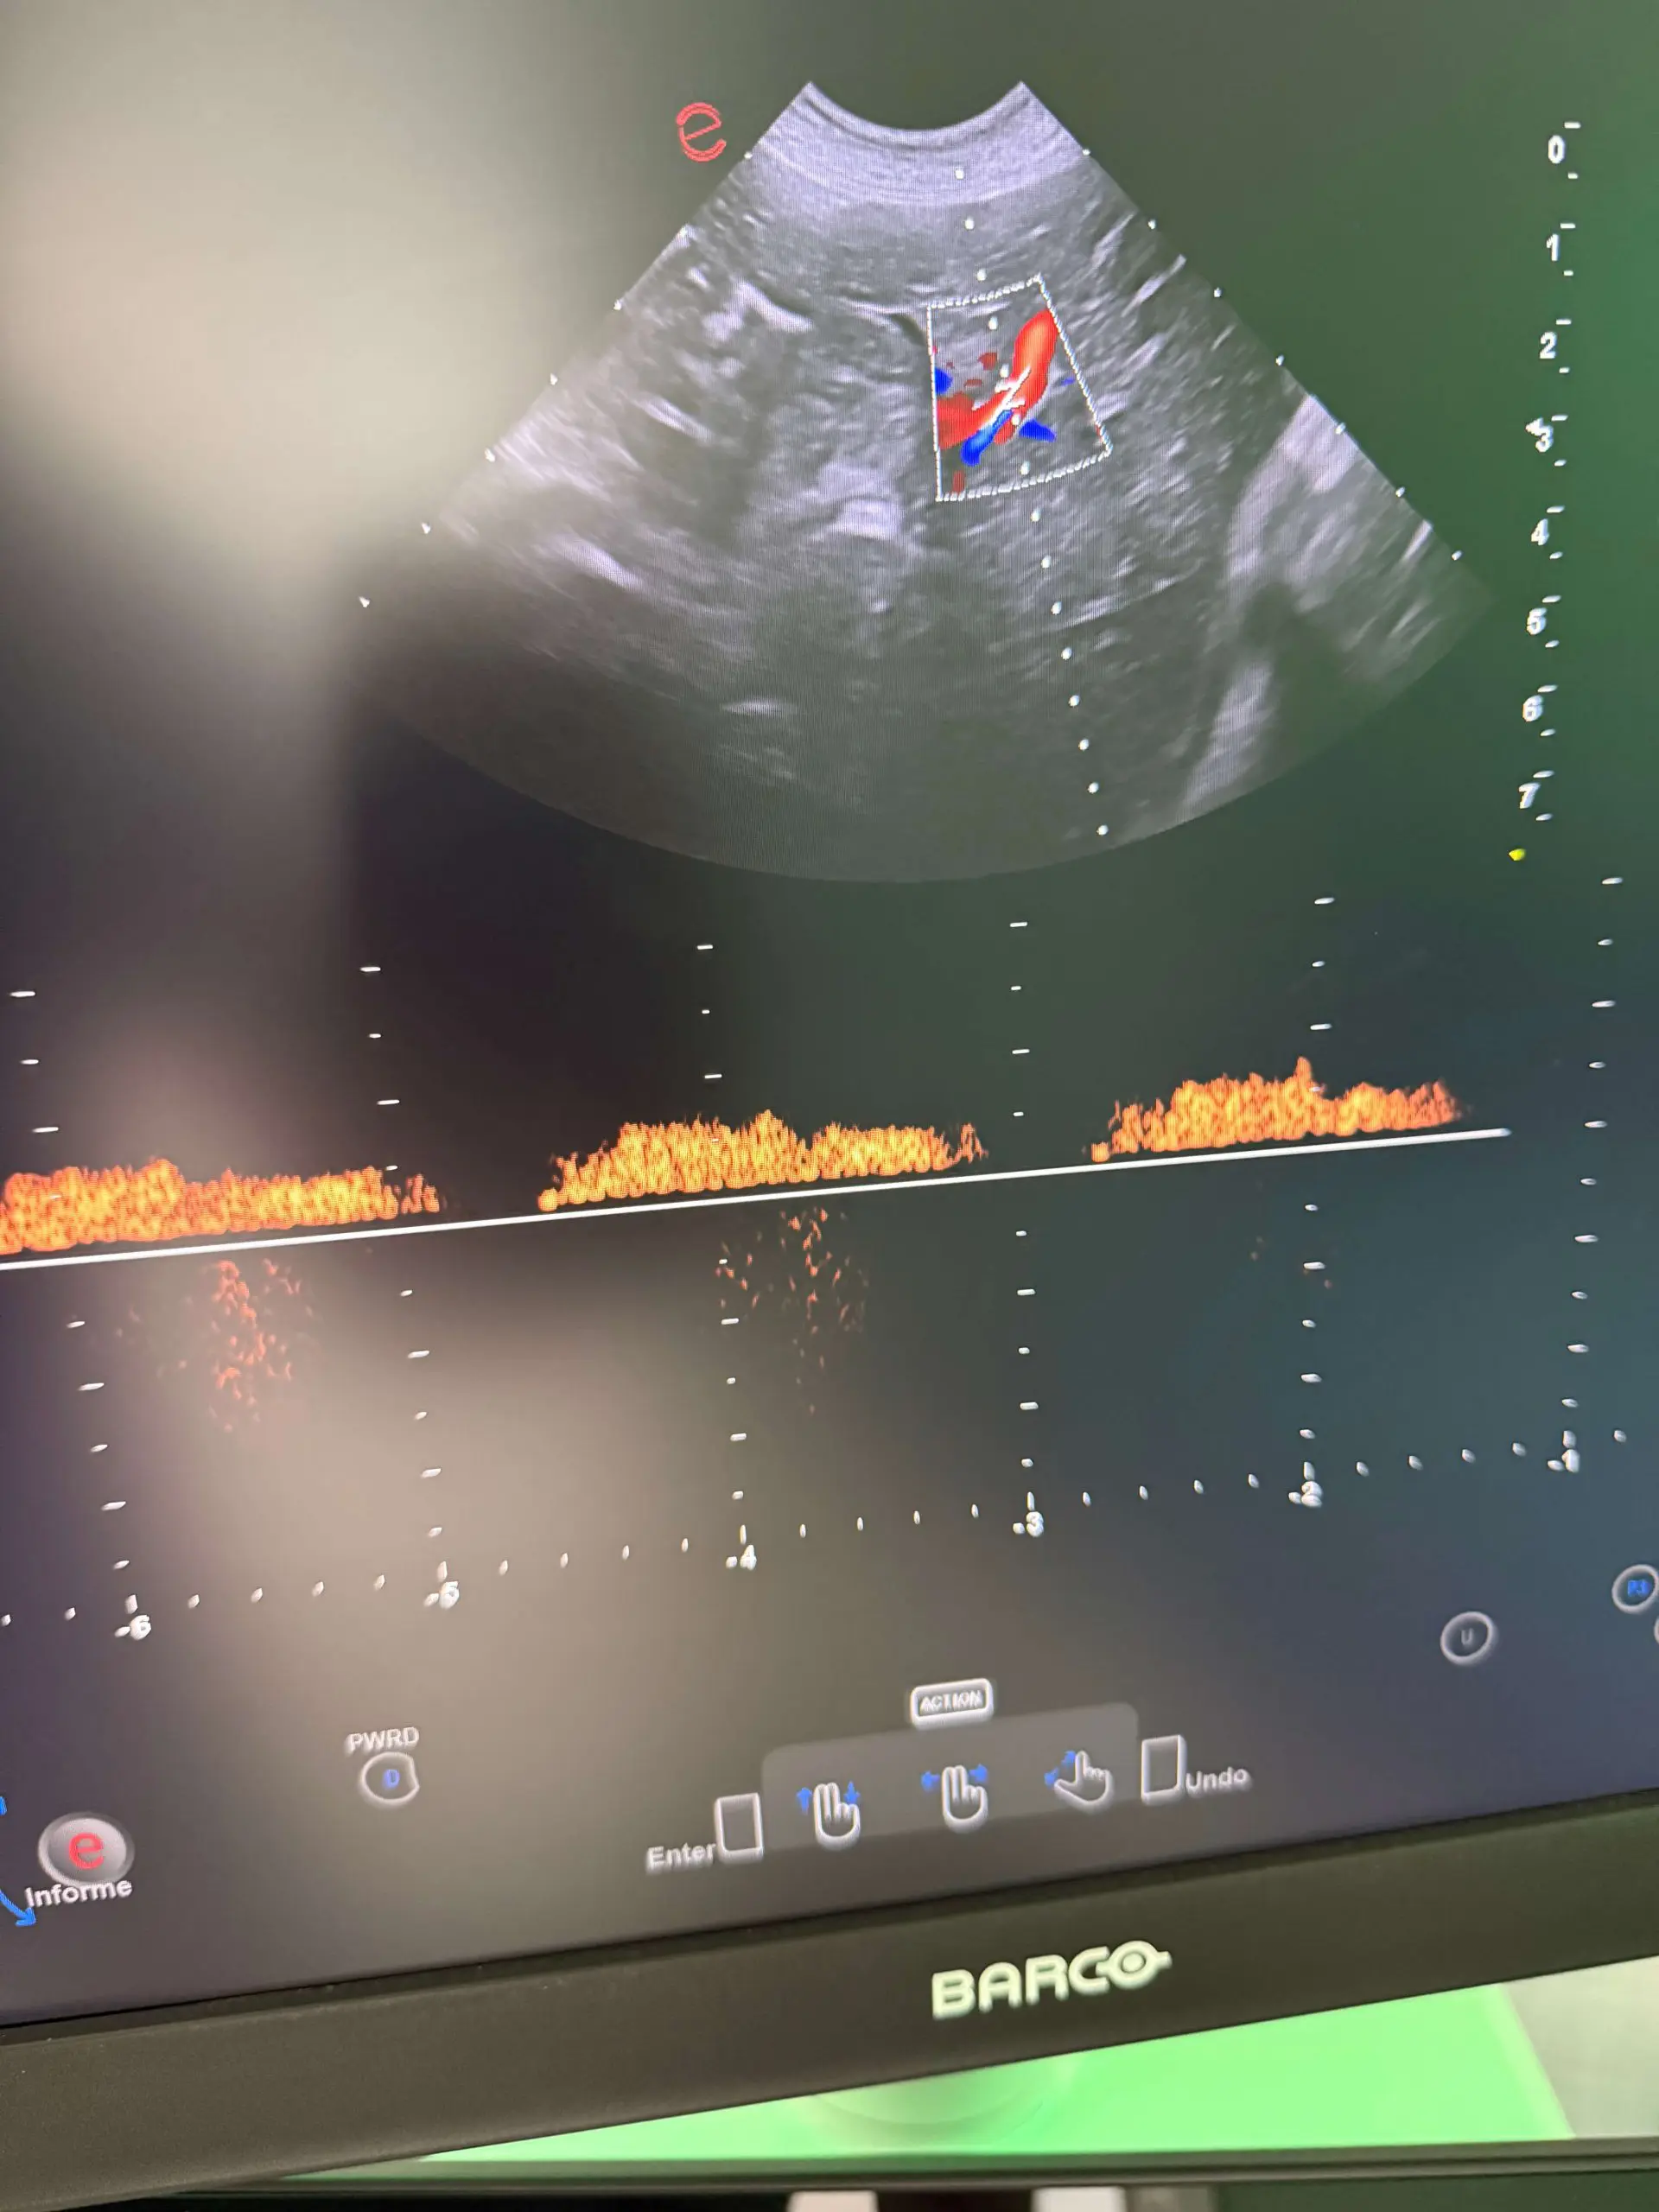

Ecocardiografía

Nos acercamos al corazón de tu mascota con la más alta precisión para valorar su funcionamiento. Este estudio permite detectar enfermedades cardíacas de forma temprana y acompañar su tratamiento con cuidado y amor.

Ecocardiografia scaled